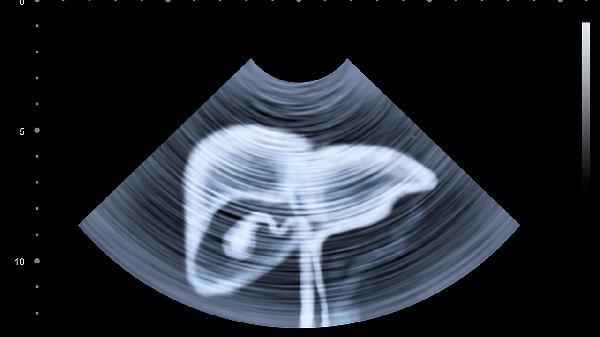

每年进行肝功能检查和肝脏超声筛查,乙肝表面抗原阴性者建议接种疫苗。存在酒精性肝损伤风险人群需监测γ-谷氨酰转肽酶指标,肝硬化高危群体应每半年检查甲胎蛋白水平。发现转氨酶持续升高应及时消化科就诊。